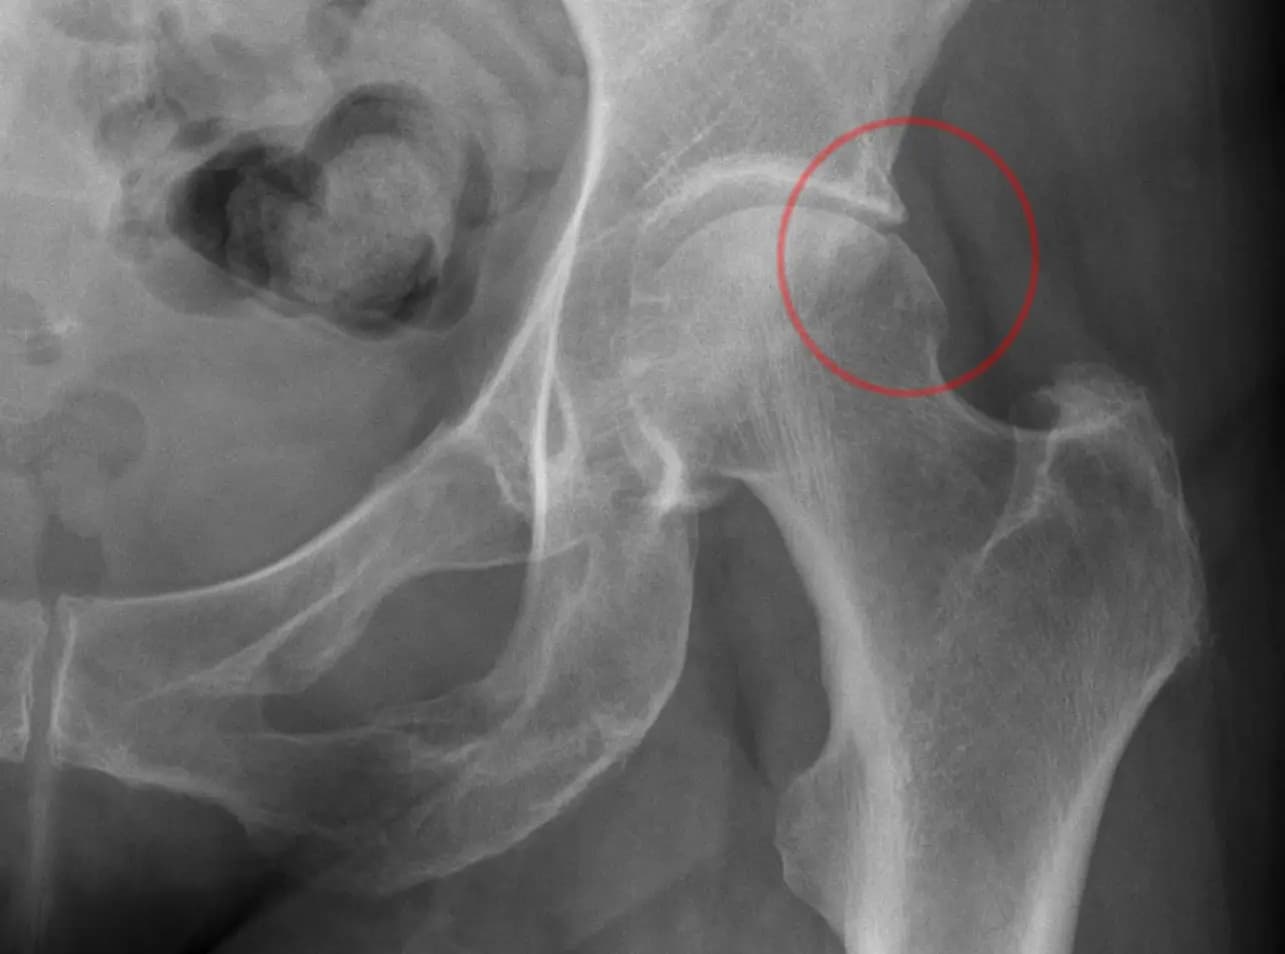

Kalça Sıkışması (Femoroasetabular Sendrom) Nedir?

Kalça sıkışması (Femoroasetabular Sendrom – FAI), kalça eklemini oluşturan kemiklerin birbirine uygunsuz şekilde...

Kalça Ağrısı Femoroasetabular Sıkışma (FAS / FAI) Nedir?

Femoroasetabular sıkışma (FAS, İng. FAI), kalça ekleminde femur başı (topuz) ile asetabulumun (soket) anormal temas...